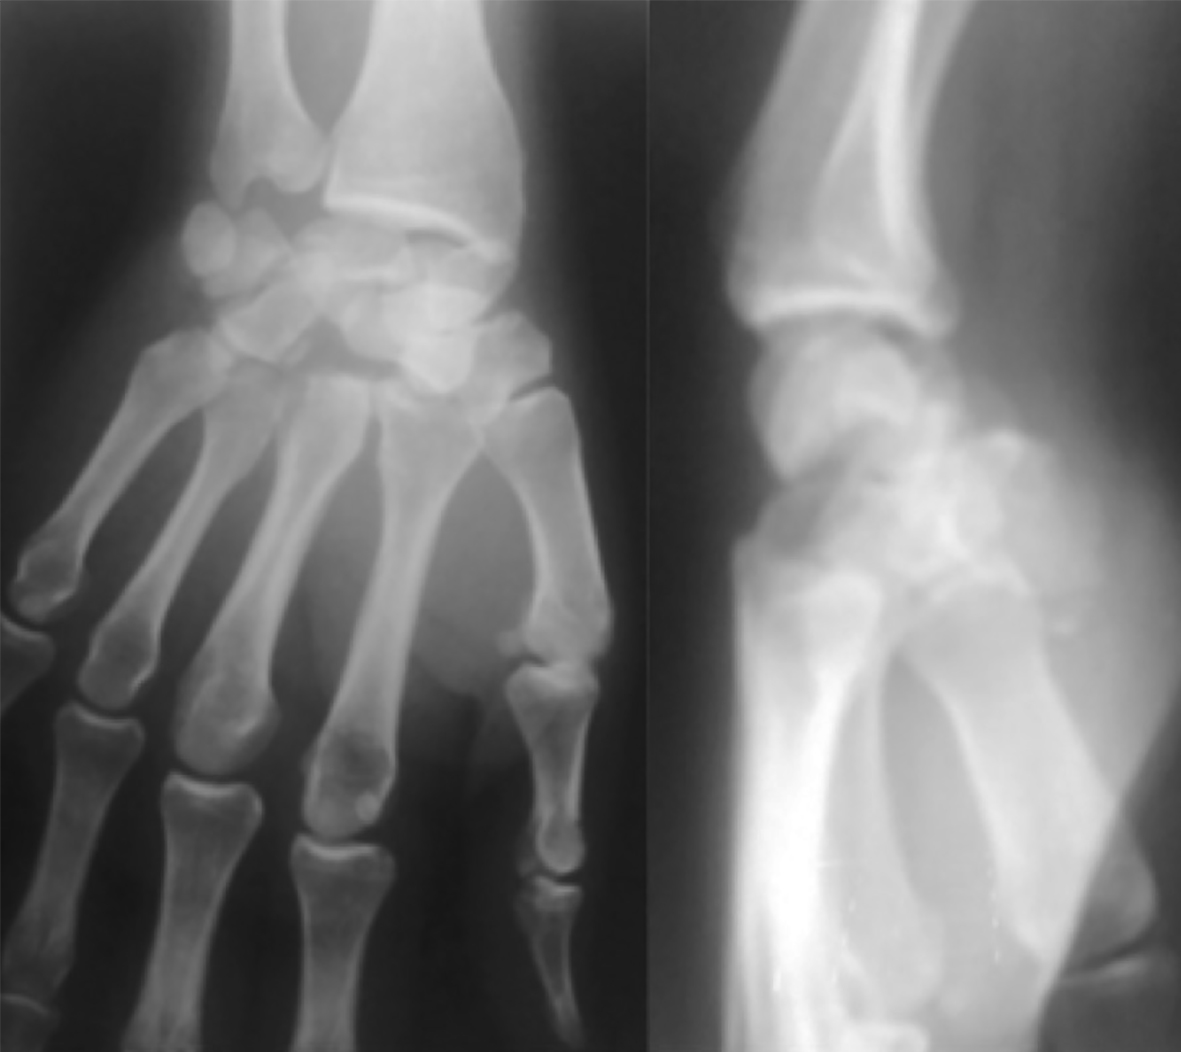

Paciente de sexo masculino, de 26 años, diestro, sin antecedentes personales a destacar, que fue embestido por automóvil mientras manejaba su moto. El paciente presentó una lesión encefálica focal que requirió tratamiento médico. Estuvo en coma 20 días, aparentemente sin otras lesiones. Luego, ya con vida de relación retomada, el paciente relató dolor e impotencia funcional de su mano derecha. Tumefacción y dolor a la movilización (pasiva-activa) y a la prehensión en el examen físico. Las radiografías y el TC mostraron una luxación volar de hueso grande de mano derecha (Figura 1) asociada a fracturas de la base del tercer metacarpiano y de hueso piramidal, ambas sin desplazamiento (Figura 2). A las 8 horas de establecer el diagnóstico se realizó una reducción abierta por vía palmar con fijación interna, con alambres de Kirchner de 1,5 mm, (Figura 3). Se agregó un mini fijador externo para proteger la estabilidad de la osteosíntesis del carpo y manejar las partes blandas lesionadas. No se realizó reconstrucción ligamentaria.

Figura 2: Cortes de TC coronal y sagital que evidencian luxación palmar de hueso grande asociada a fractura del piramidal y base del segundo y tercer metacarpiano.